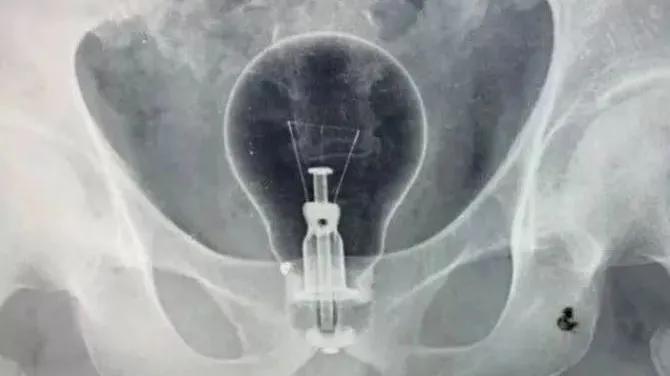

灯泡、茄子、花露水瓶、……

西南医科大学附属中医医院肛肠科主任李五生教授说:直肠异物是直肠里出现除了粪便以外的其他东西,比如灯泡、按摩棒、玻璃药瓶、陀螺、蜡烛、圆柱形金属瓶等等,甚至常见的蔬菜和长条状的物体,比如黄瓜、火腿肠、茄子、苦瓜、黄鳝、泥鳅……